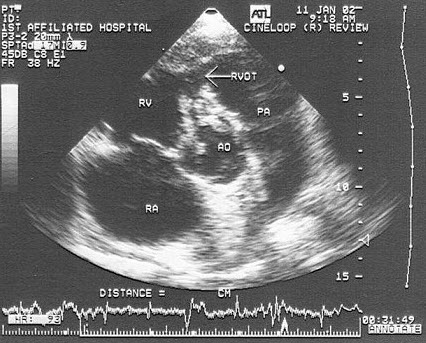

患者反复发热,原有先心病史,该病例最有可能诊断( )

A:室缺并感染性心内膜炎

B:主动脉瓣脱垂

C:窦瘤破裂

D:右流狭窄

E:肺动脉瓣狭窄